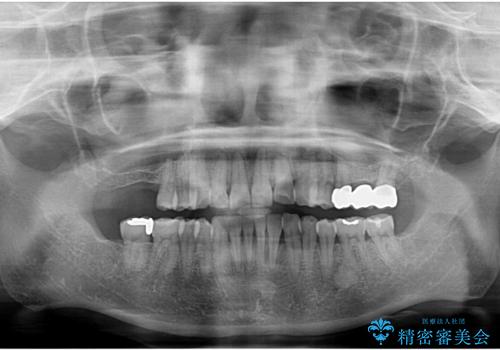

奥歯も少なく、左上奥歯はブリッジにすることになりました。

- 140.8万円(矯正治療:104.5万円、奥歯ブリッジ:36.3万円[ジルコニアクラウン10万円x3 仮歯x1万円x3])費用は治療当時の料金となります

右上大臼歯2本の欠損については、インプラント治療をお勧めしましたが、ご希望によりそのままとなりました。